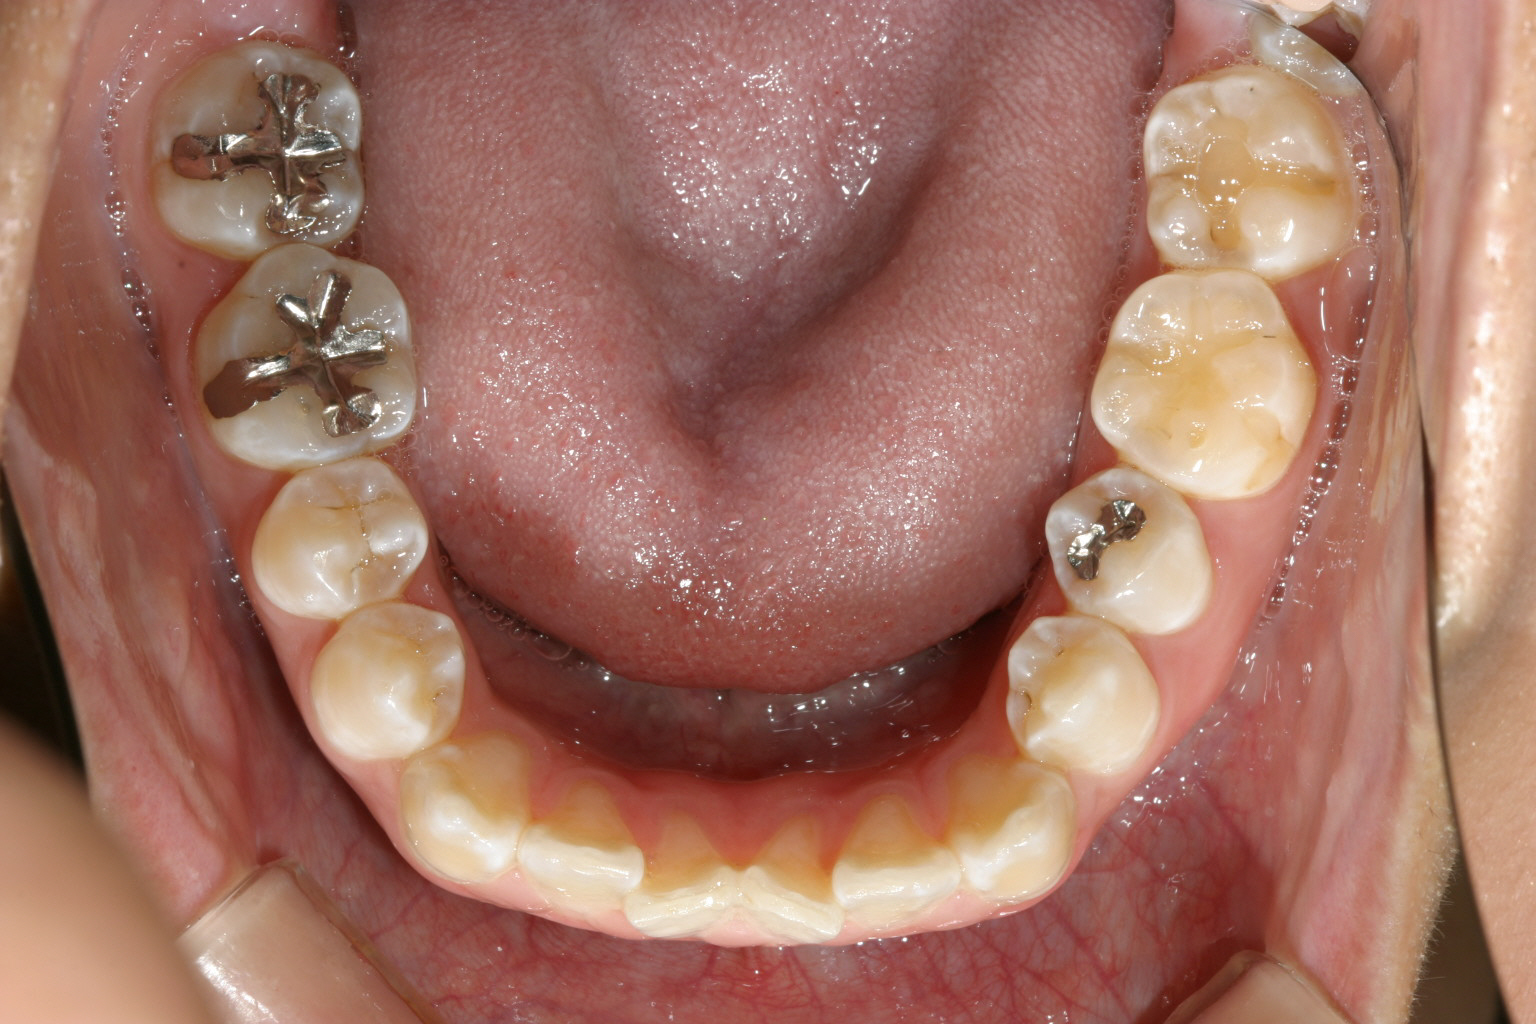

マルチループワイヤー使用で3ヵ月です。 もう殆ど犬歯の飛び出し改善してます。

下顎もマルチループワイヤーしています。

前から見るとこんな感じです。 ちょっと見栄え悪すぎですかね~